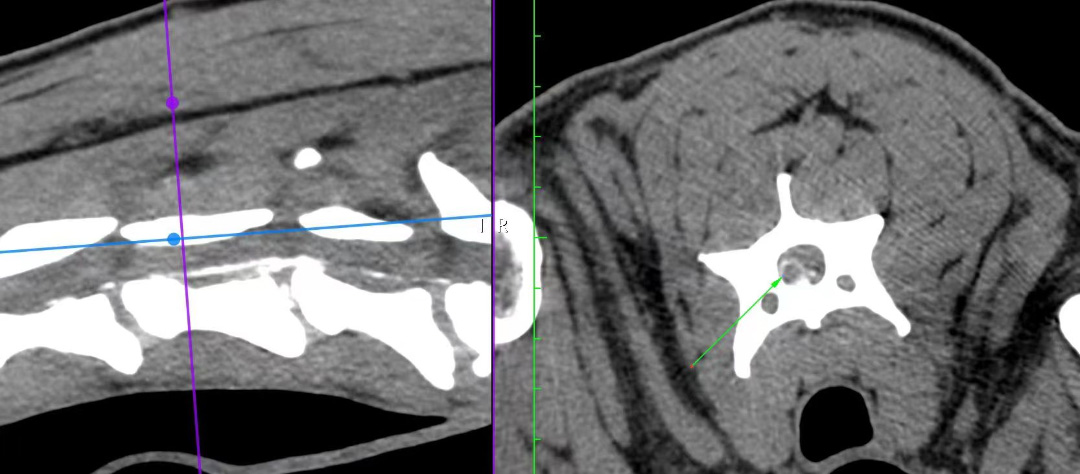

摘要:路卡、边牧串、雄性(未去势)、9岁。患犬2023年2月底洗澡后倒地不起,前肢关节肿胀,不吃不喝,CT检查发现椎间盘突出导致瘫痪。中兽医检查及辨证为肾阳虚,脾气虚,膀胱湿热,瘀滞。经过中兽医(针灸、中药)治疗,患犬能够小跑一段,主人比较满意。 宠物信息:路卡,雄性,9岁,边牧串,体重21kg。 既往病史:该犬1岁时得过细小,8岁有尿结石手术病史,2023年2月底刚去乡下几天